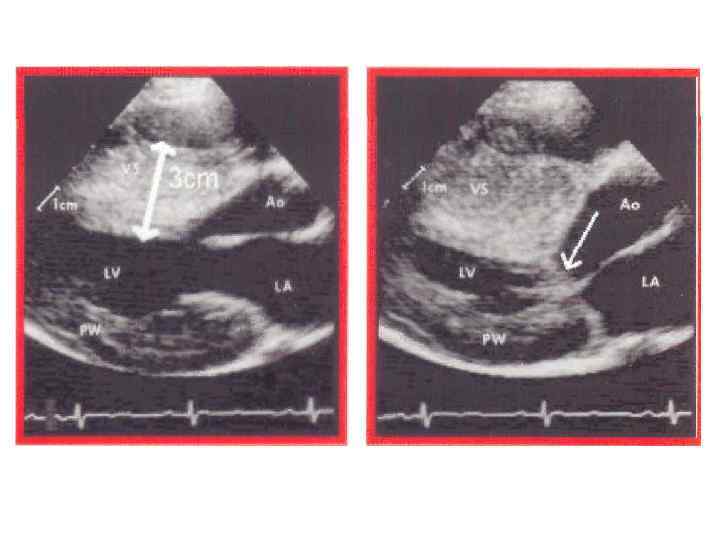

ГКМП • Классификация ГКМП Идиопатический субаортальный стеноз • II. Асимметричная гипертрофия межжелудочковой перегородки • III. Верхушечная КМП • IV. Симметричная КМП • I.

ГКМП • Классификация ГКМП Идиопатический субаортальный стеноз • II. Асимметричная гипертрофия межжелудочковой перегородки • III. Верхушечная КМП • IV. Симметричная КМП • I.

Гипертрофическая кардиомиопатия • • • одышка при физической нагрузке боли в груди, которые могут быть стенокардитического характера сердцебиение и синкопальные состояния внезапная сердечная смерть систолический шум, который может быть различным - от средне- до позднесистолического, и IV сердечный тон, интенсивность систолического шума возрастает, когда больной встает, а также в фазе напряжения при пробе Вальсальвы электрокардиографические признаки гипертрофии левого предсердия и левого желудочка, зубцы Q в отведениях V 4 -V 6 , Q в II, III, AVF отведениях, появление которых связывают с гипертрофией верхней трети межжелудочковой перегородки

Гипертрофическая кардиомиопатия • • • одышка при физической нагрузке боли в груди, которые могут быть стенокардитического характера сердцебиение и синкопальные состояния внезапная сердечная смерть систолический шум, который может быть различным - от средне- до позднесистолического, и IV сердечный тон, интенсивность систолического шума возрастает, когда больной встает, а также в фазе напряжения при пробе Вальсальвы электрокардиографические признаки гипертрофии левого предсердия и левого желудочка, зубцы Q в отведениях V 4 -V 6 , Q в II, III, AVF отведениях, появление которых связывают с гипертрофией верхней трети межжелудочковой перегородки

ФР риска ВС при ГКМП • Молодой возраст < 30 лет в момент установления диагноза • Семейный анамнез ГКМП со случаями ВС • Желудочковая тахикардия • Частые повторные синкопальные состояния • Массивная гипертрофия ЛЖ • Генетические аномалии, ассоциированные с высокой частотой ВС • Выраженная дилатация ЛП

ФР риска ВС при ГКМП • Молодой возраст < 30 лет в момент установления диагноза • Семейный анамнез ГКМП со случаями ВС • Желудочковая тахикардия • Частые повторные синкопальные состояния • Массивная гипертрофия ЛЖ • Генетические аномалии, ассоциированные с высокой частотой ВС • Выраженная дилатация ЛП